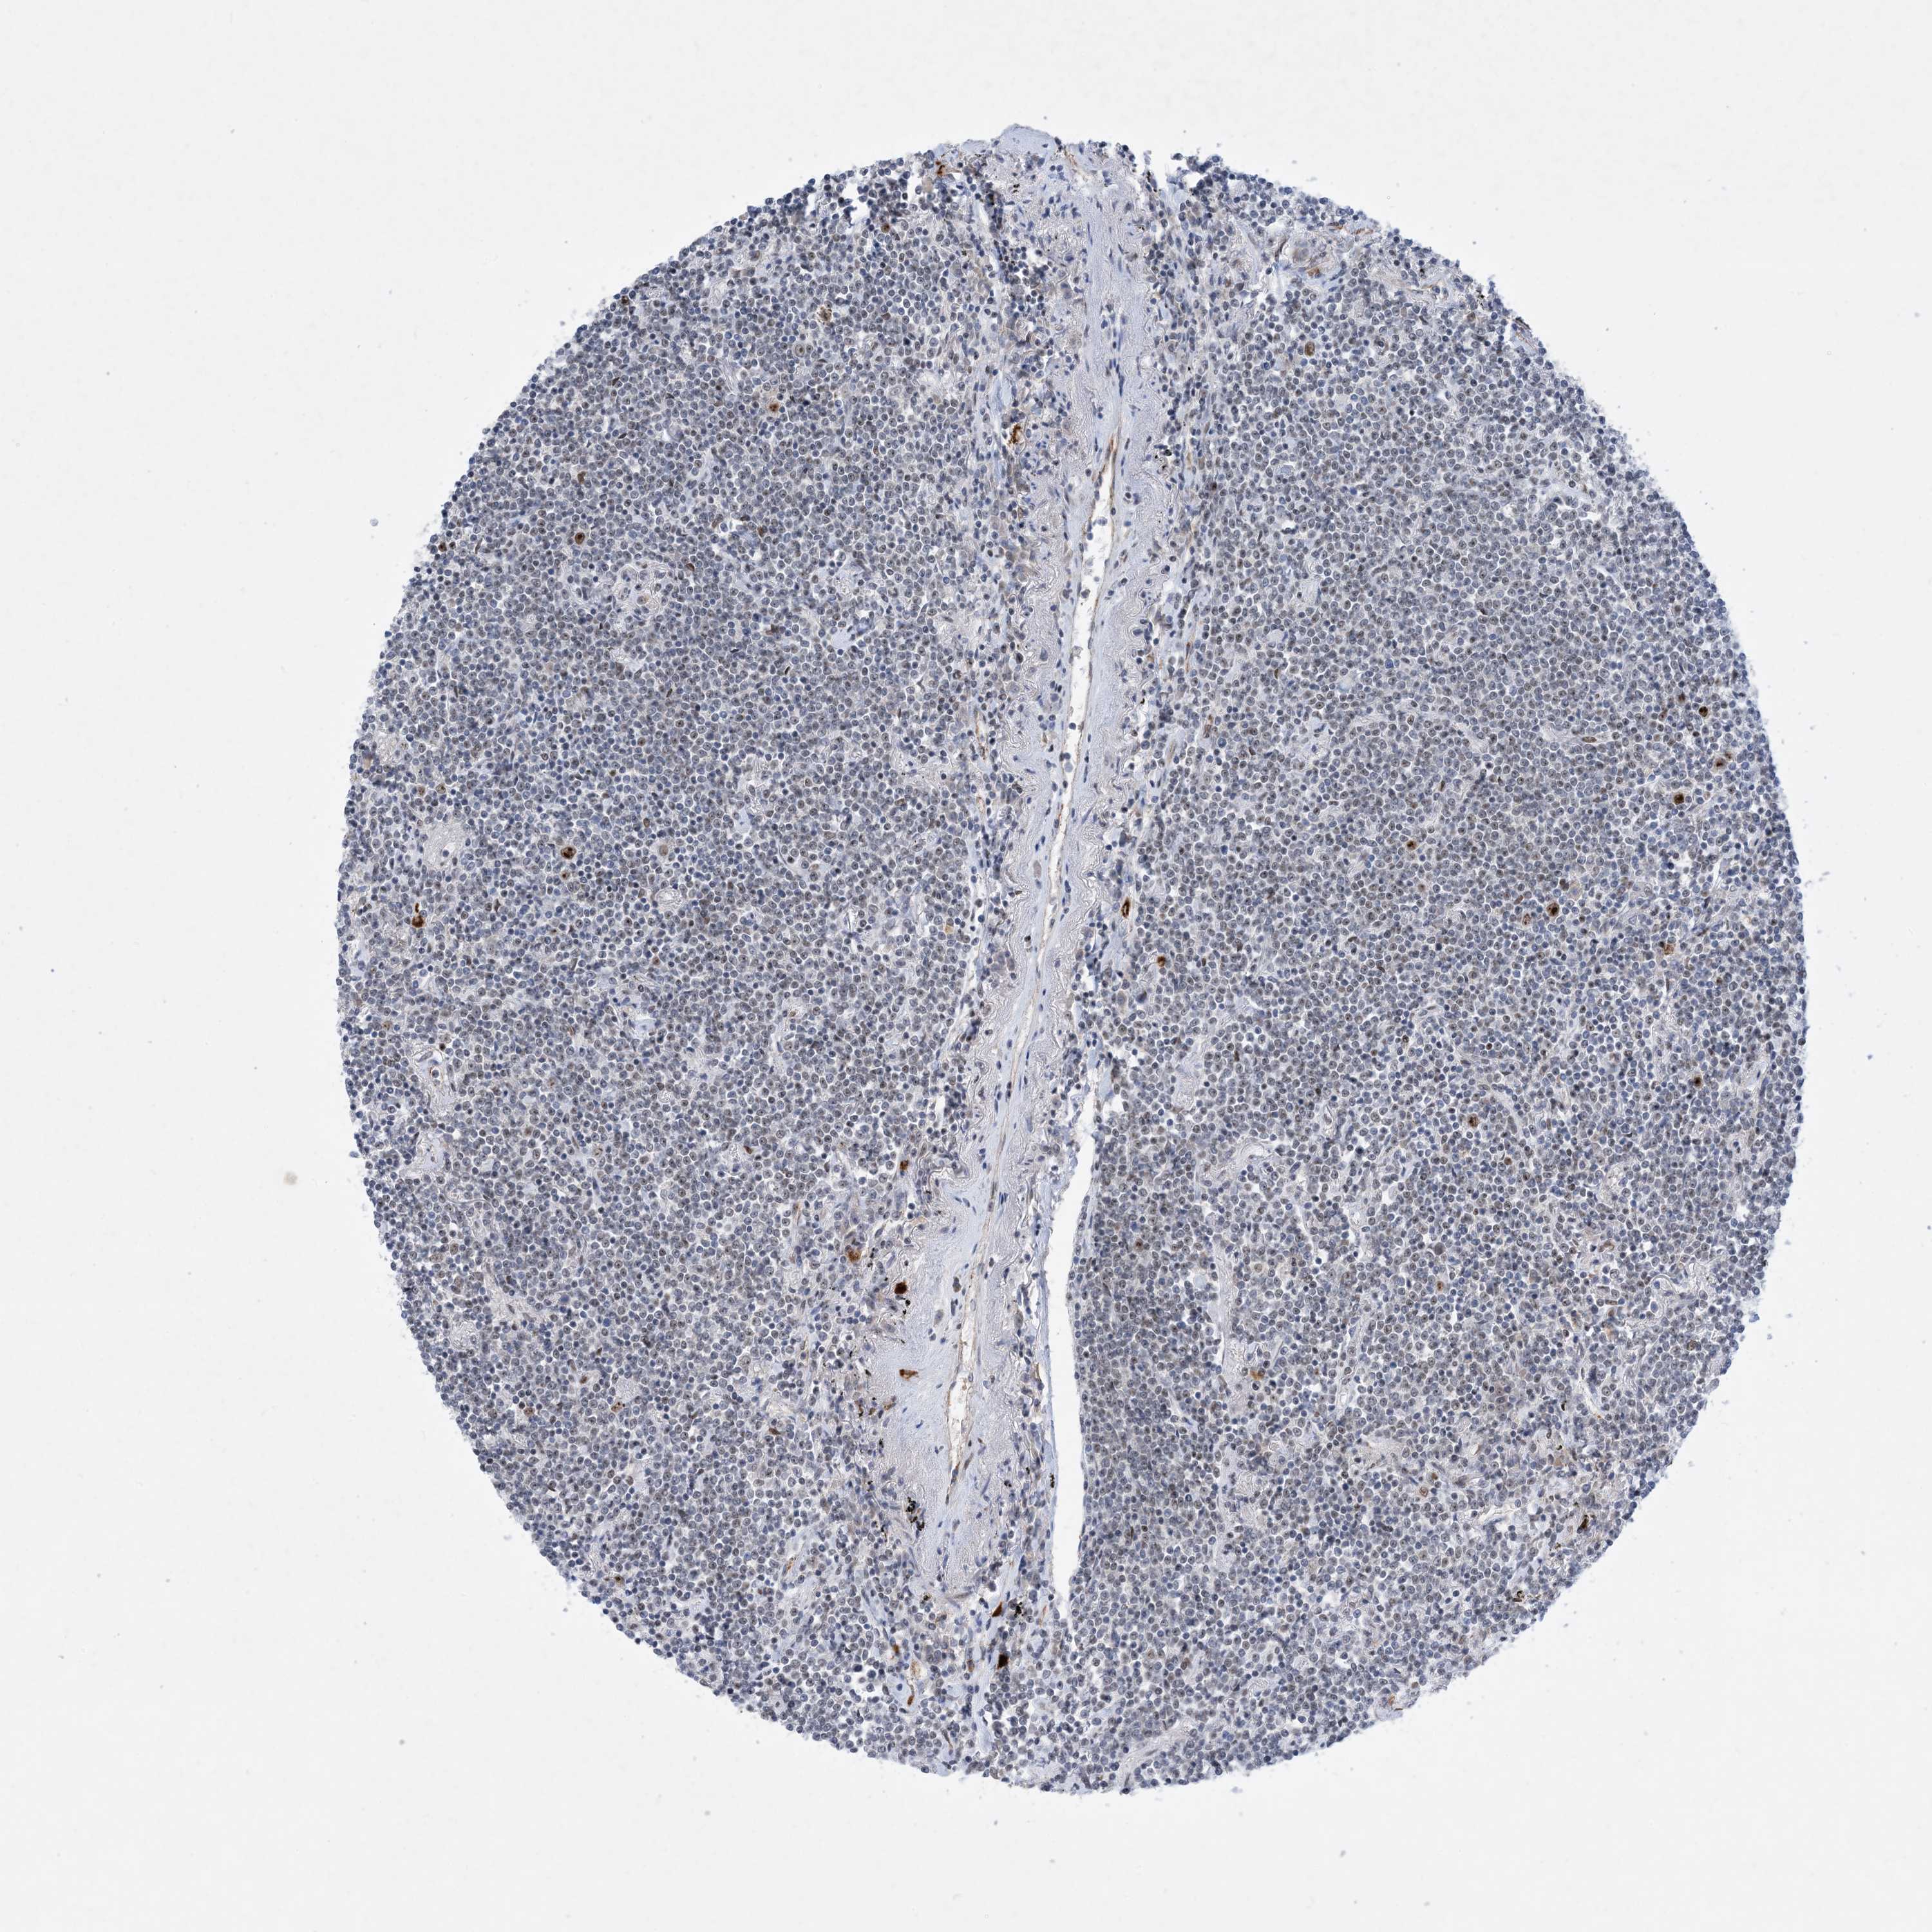

LYMPHOMA - Protein expressioni

A mouse-over function shows sample information and annotation data. Click on an image to view it in a full screen mode. Samples can be filtered based on level of antibody staining by selecting one or several of the following categories: high, medium, low and not detected. The assay and annotation is described here.

Antibody stainingi

Antibody staining in the annotated cell types in the current human tissue is reported as not detected, low, medium, or high, based on conventional immunohistochemistry profiling in selected tissues. This score is based on the combination of the staining intensity and fraction of stained cells.

Each image is clickable and will lead to virtual microscopy that enables deeper exploration of all samples and also displays staining intensity scores, fraction scores and subcellular localization as well as patient and tissue information for each sample.

Antibody HPA031970

Hodgkin's disease, NOS

Malignant lymphoma, non-Hodgkin's type, High grade

Malignant lymphoma, non-Hodgkin's type, Low grade